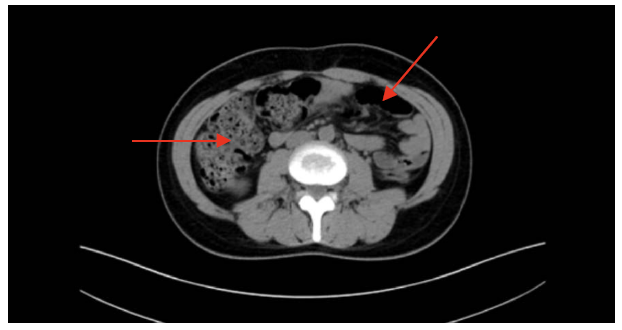

干燥综合征(Sjögren syndrome, SS)是一种以外分泌腺受累为主的系统性自身免疫性疾病,临床表现多样,易被误诊。本文报道1例以假性肠梗阻(intestinal pseudo-obstruction, IPO)为首发症状的SS病例。患者为31岁女性,因恶心、呕吐伴排便停止就诊,影像学提示结肠积粪但无机械性梗阻证据,血清学检测显示抗SSA/SSB/Ro-52抗体阳性,唇腺活检符合SS特征。经糖皮质激素及免疫调节治疗后症状缓解。本病例提示,SS可表现为非典型胃肠及神经系统症状,临床中需结合自身抗体检测及多学科评估以提高诊断准确性。